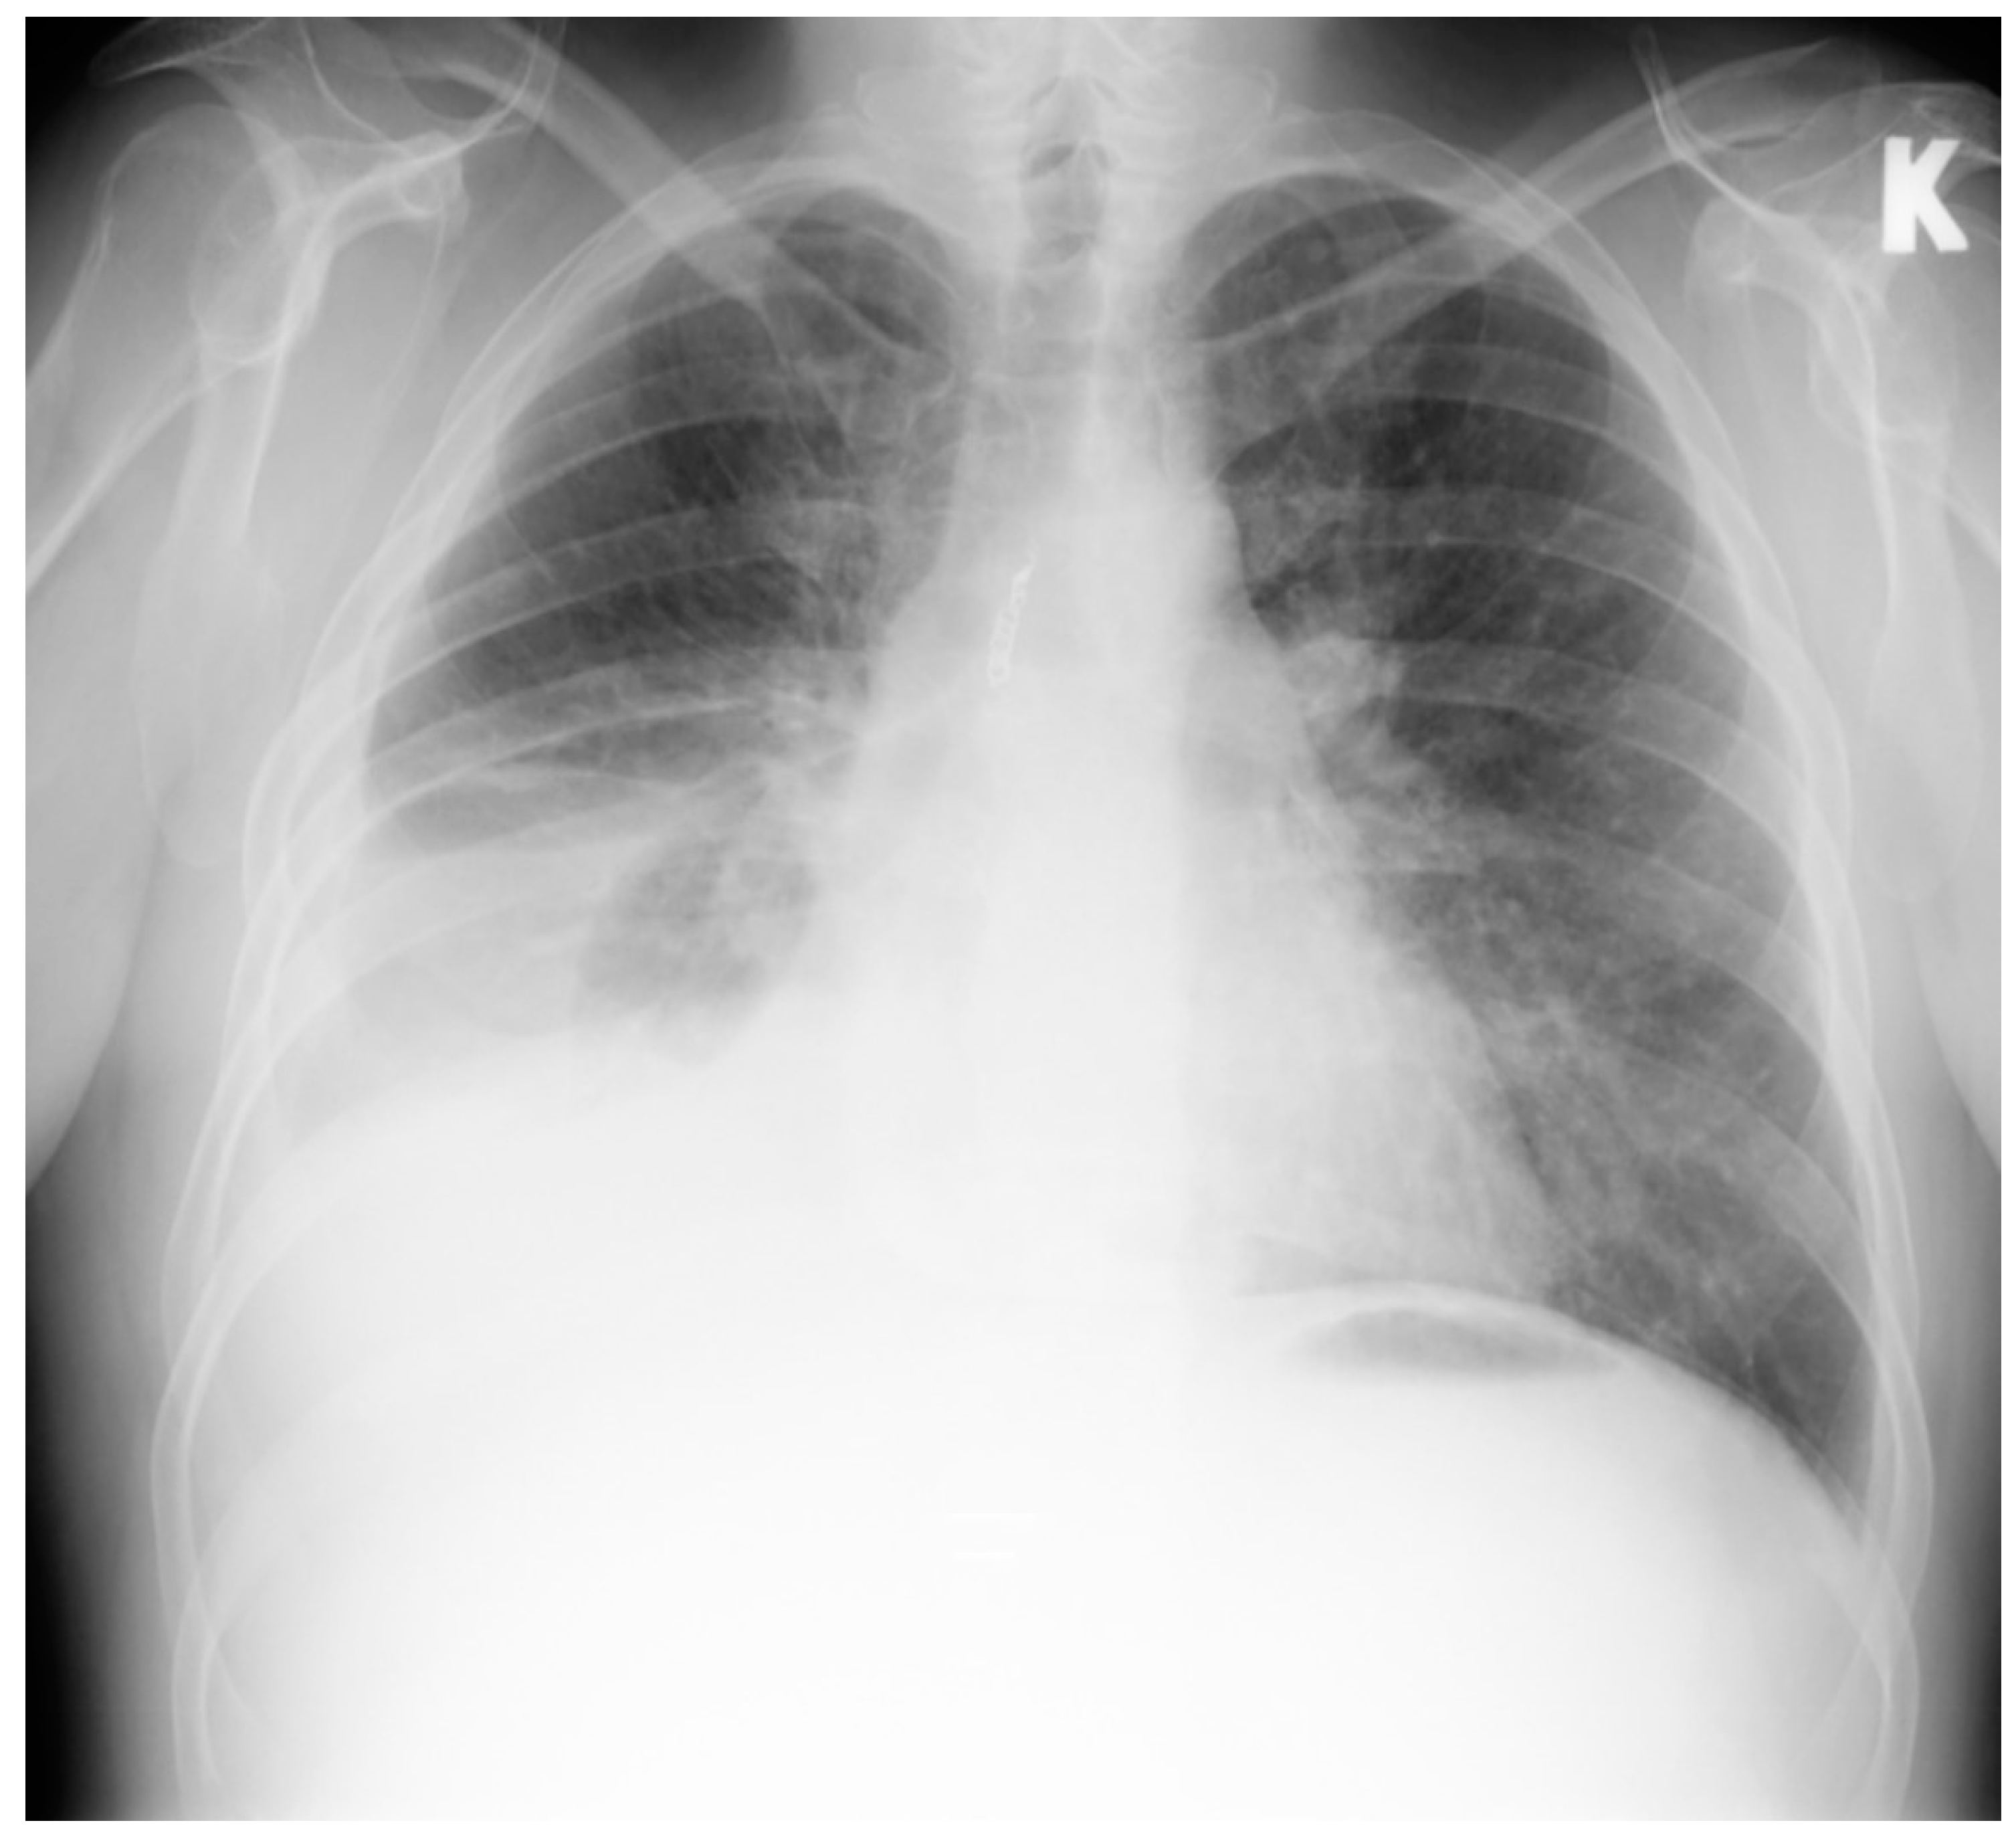

NT-proBNP was more than 1500 ng/L, other blood tests were normal. Chest X-ray showed right side hydrothorax up to the sixth rib (Figure 1).

Figure 1. Chest X-ray. Right side hydrothorax. K-left side.